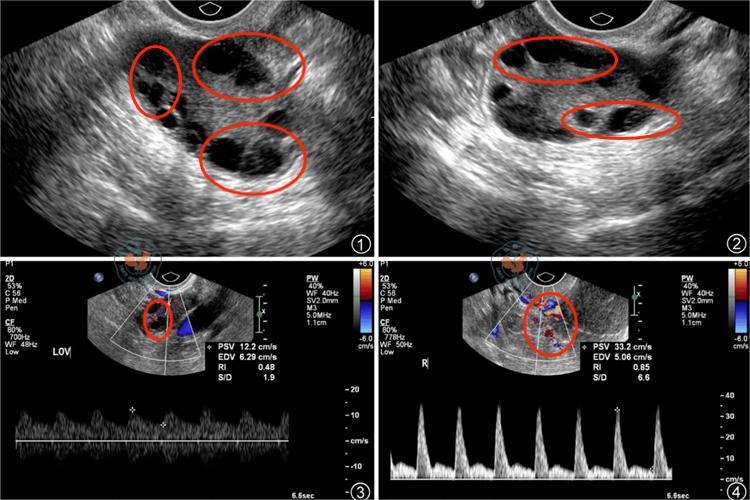

此外,多囊卵巢综合征可导致患者无排卵或稀发排卵,大多数伴有月经紊乱,主要的临床表现形式为闭经、月经稀发和功能失调性子宫出血等。由于排卵受到障碍,多囊卵巢综合征的患者受孕率降低,流产率增高。

治疗方法主要是促进排卵,减少雄激素生成,治疗不孕。以药物治疗为主,无效时可在腹腔镜下将各卵泡穿刺、电凝或激光,使卵泡液外溢,血中雌激素、孕激素可下降,通过反馈作用使促卵泡激素上升,从而卵泡发育成熟及排卵。